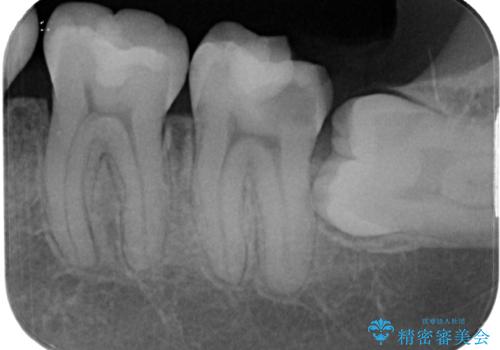

- 左下の奥歯が欠けたとのことで来院された患者様です。検査の結果、埋まっている親知らず抜歯とその手前の左下の7番目の歯のフルジルコニアクラウンによる補綴治療をおこなっていくこととしました。

左下の虫歯が大きいため、神経のテストも行いましたが正常な反応を示しました。

左下の虫歯が歯茎の下にも広がっているので、歯茎の位置を下げるためディスタルウェッジを行い埋伏親知らず抜歯を行いました。また同日に左下の歯を仮歯に変えています。

歯茎の治癒を3か月程度待ち、最終的なフルジルコニアクラウンの形に整え精密な型どりをシリコーン印象材にて行っております。